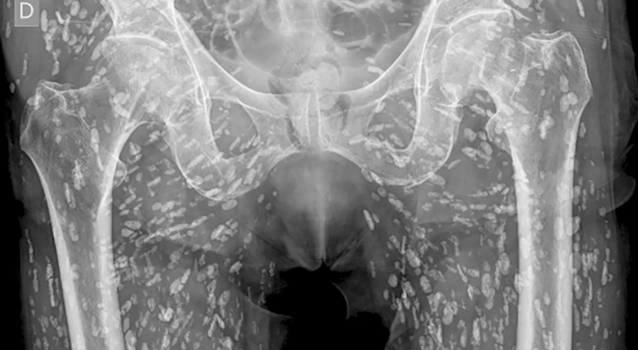

‘This is one of the most insane X-rays I’ve ever seen’

A doctor has shared stomach-turning X-ray images of a man who had tapeworms breeding inside of him after he made a serious kitchen error.

Sam Ghali, an Assistant Professor in Emergency Medicine at the University of Florida, shared the shocking images in a post on X, saying it was “one of the most insane X-Rays I’ve ever seen.”

Speaking over the X-Ray pictures, Dr Ghali explained that the small white marks were dozens of calcified tapeworm eggs, which had been laid in the soft tissue of the man’s pelvis.

The parasitic worms had made their way into the man’s body after he at undercooked pork, a condition is known as cysticercosis.

This is where larval cyst of taenia solium make their way into the body. Once there, they can burrow into muscular and soft tissue and travel “throughout the entire body,” Dr Ghali said.

He explained: “These cysts can travel anywhere throughout the entire body, heavily to the muscular and soft tissue of the hips and the legs. This condition comes from when the patient eats undercooked, or raw, pig. If just in the pelvis, they don’t pose a life-threatening problem. The problem is if they travel to the brain and lodge there.

“That can cause very serious issues. As you can imagine, that can lead to neurological symptoms like headaches, confusion, seizures and even death. The moral of the story is never eat raw pork.”